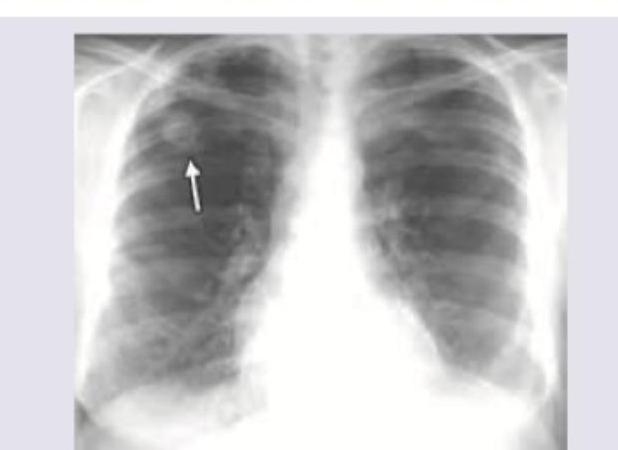

A 35-year-old crane operator at construction site with pre-existing seropositive rheumatoid arthritis complains of progressive difficulty in breathing. Chest X-ray was performed. What is the diagnosis?

Explanation: ***Caplan syndrome*** - The combination of **seropositive rheumatoid arthritis**, occupational exposure in a **coal mine** (crane operator at a construction site implies exposure to dust/silica), and the presence of **pulmonary nodules** on chest X-ray are classic features of Caplan syndrome. - This syndrome is a pneumoconiosis characterized by the development of distinctive, often large, well-defined **rheumatoid nodules** in the lungs of individuals with RA and simultaneous exposure to industrial dusts like coal or silica. *Felty syndrome* - Felty syndrome is a rare, severe complication of rheumatoid arthritis characterized by the triad of **rheumatoid arthritis**, **splenomegaly**, and **neutropenia**. - While it occurs in individuals with seropositive RA, it does not directly involve primary pulmonary consolidation or nodules as the main presenting feature. *Bronchiolitis obliterans organizing pneumonia* - This is a form of lung disease characterized by inflammation of the small airways and surrounding alveolar spaces, often presenting with **cough**, **dyspnea**, and **flu-like symptoms**. - Radiographically, it typically shows **patchy alveolar opacities** or **consolidation**, which is different from the distinct nodules seen in the image and characteristic of Caplan syndrome. *Lung cancer* - While lung cancer can manifest as a **pulmonary nodule** and cause dyspnea, the patient's history of **seropositive rheumatoid arthritis** and occupational exposure to dust strongly points towards an inflammatory-rheumatic etiology rather than primary malignancy. - The context of a pre-existing systemic autoimmune disease and specific occupational exposure makes **Caplan syndrome** a more specific and likely diagnosis given the radiologic findings.